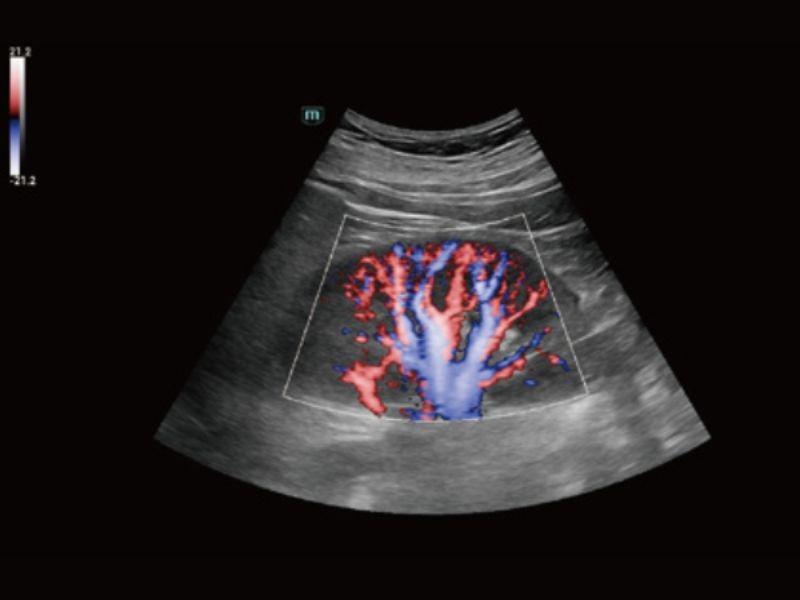

Solução de imagem geral

Medição IMT em tempo real baseada em dados de RF

R-VQS

Coeficiente de dureza vascular e velocidade da onda de pulso (PWV)